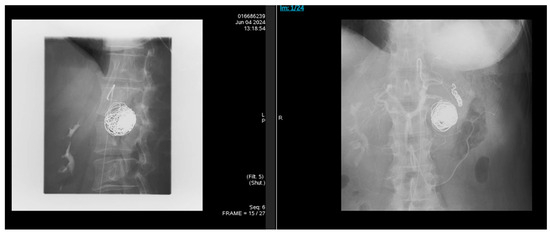

Background and Clinical Significance: Splenic artery pseudoaneurysm (SAP) is a rare but life-threatening complication of chronic pancreatitis. Although endovascular embolization achieves high technical success, recurrence and delayed rupture may occur, particularly in patients with ongoing pancreatic inflammation or alcohol use disorder (AUD). Case Presentation: A 47-year-old woman with alcohol-associated chronic pancreatitis presented with hematochezia, melena, and syncope. CT angiography revealed a 3.6 cm SAP adjacent to a 4.2 cm pancreatic head pseudocyst, and she underwent successful coil embolization. Despite initial stability, she relapsed into heavy alcohol use, experienced recurrent pancreatitis flares, and developed progressive multisystem comorbidities. Surveillance imaging up to three months post-embolization showed pseudocyst fluctuations without early recanalization, but long-term follow-up lapsed. Eight months after embolization, she presented in hemorrhagic shock from recurrent SAP rupture and died despite massive transfusion and emergent splenic artery ligation. Conclusions: Fatal SAP rupture may occur months after technically successful embolization. Sentinel bleeding, AUD relapse, and progressive systemic decline are critical warning signs. Structured post-embolization imaging and multidisciplinary management are essential to improve long-term outcomes. Full article

Figure 1